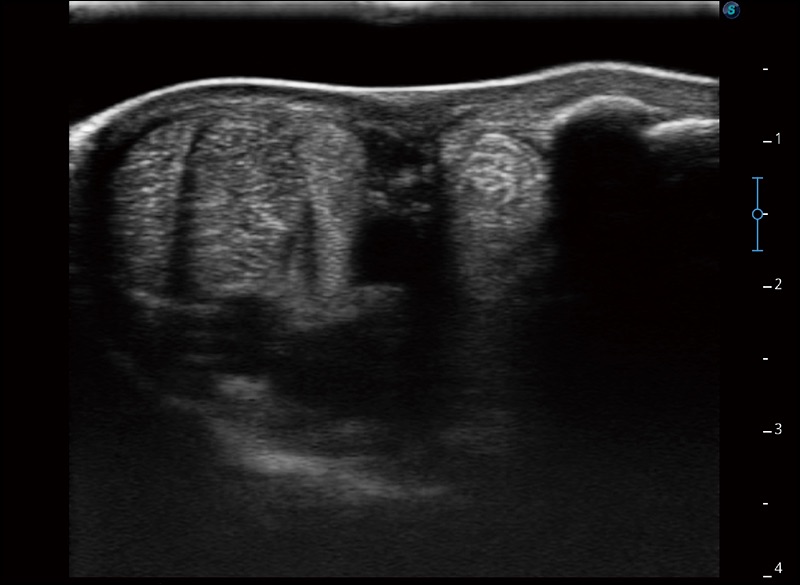

实时宽景成像

可实时观察感兴趣区域和病变位置